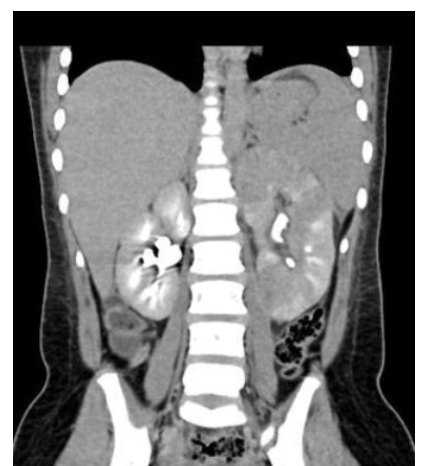

what is the diagnosis

L sided hydronephrosis